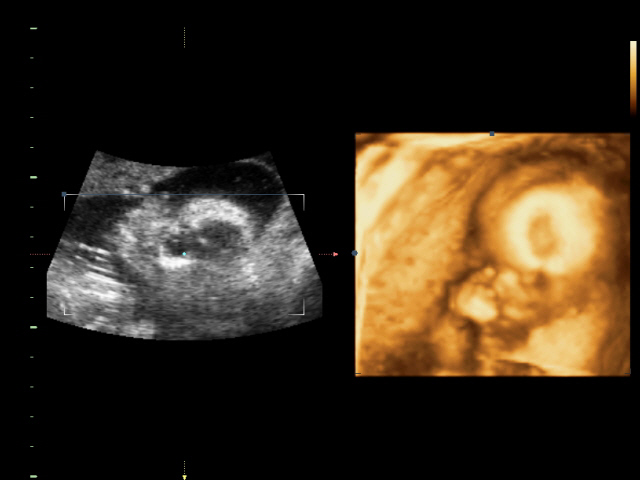

УЗИ, КТГ, доплерСходили всей семьей на 4D УЗИ! Определили нам пол окончательно и бесповоротно! Мальчик! Показали писюн! Так здорово! Я просто поверить не могу! А ведь он мне два раза снился! Настоящий реальный мужчина! Все показатели у нас в норме.